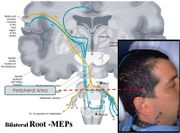

| 18:03, 15 February 2022 | Bilateral Root-MEPs.jpg (file) |  |

71 KB | Admin | ==Dettagli== {{CF | Descrizione = ''electrical Transcranial Stimulation: Schematic and anatomical representation.'' | Fonte = {{SF}} | Data = | Autore = {{augf}} | Licenza = {{Cc-by-sa-4.0}} }} Category:Explanatory files | 1 |